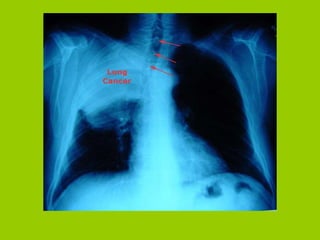

Normal Lung vs. Cancerous Lung

Normal Lung vs.Cancerous Lung

Lung Cancer—Early Signs(#1) Persistent, productive cough, dyspnea, wheezing Detection on chest X-ray Hemoptysis Pleural involvement Chest pain Hoarseness Facial, arm edema; headaches Dysphagia

Lung Cancer—Diagnostic Tests Chest X-rays Bronchoscopy Pulmonary function tests